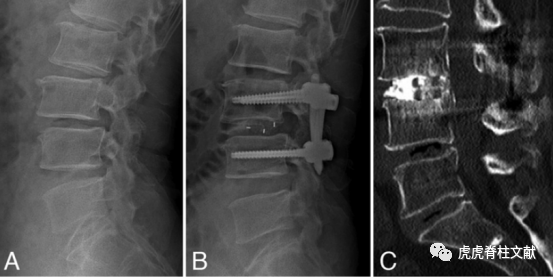

4.A:术前侧位片显示退行性腰椎滑脱症,L3-4处椎间盘间隙变窄。B:全内镜椎间融合术后侧位X线。C:术后14个月矢状位CT图像,显示椎间融合